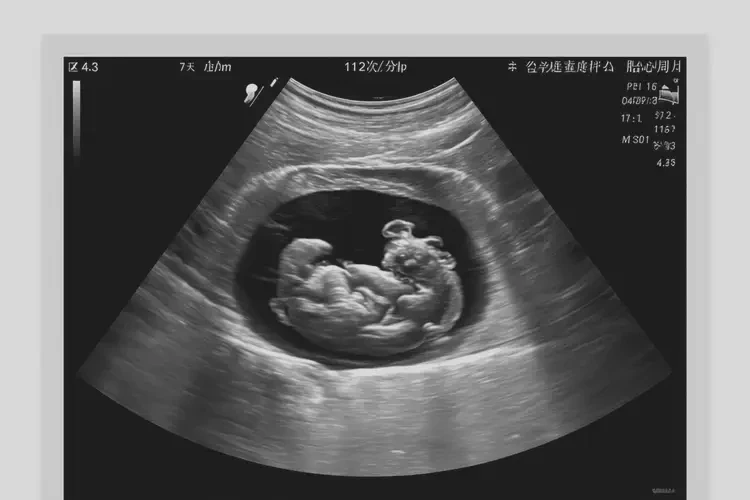

112次/分钟

在孕7周3天时,胎心112次/分钟 属于正常范围。胎心率的正常范围通常在 110-160次/分钟,个体差异和测量误差可能导致胎心率在一定范围内波动。

在孕7周3天时,胎心112次/分钟 处于正常范围,孕妇无需过于担心。但若出现胎心率持续异常或其他不适症状,应及时就医,以确保胎儿健康。